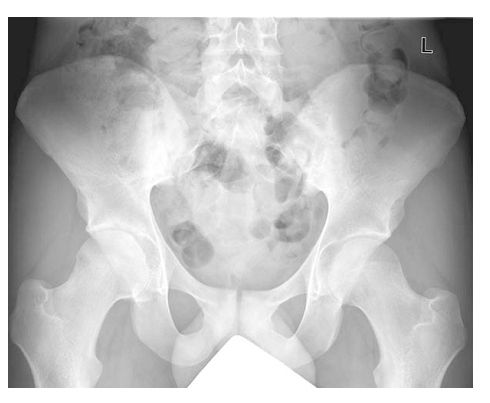

Остеит лонного сочленения симптомы - фото презентация